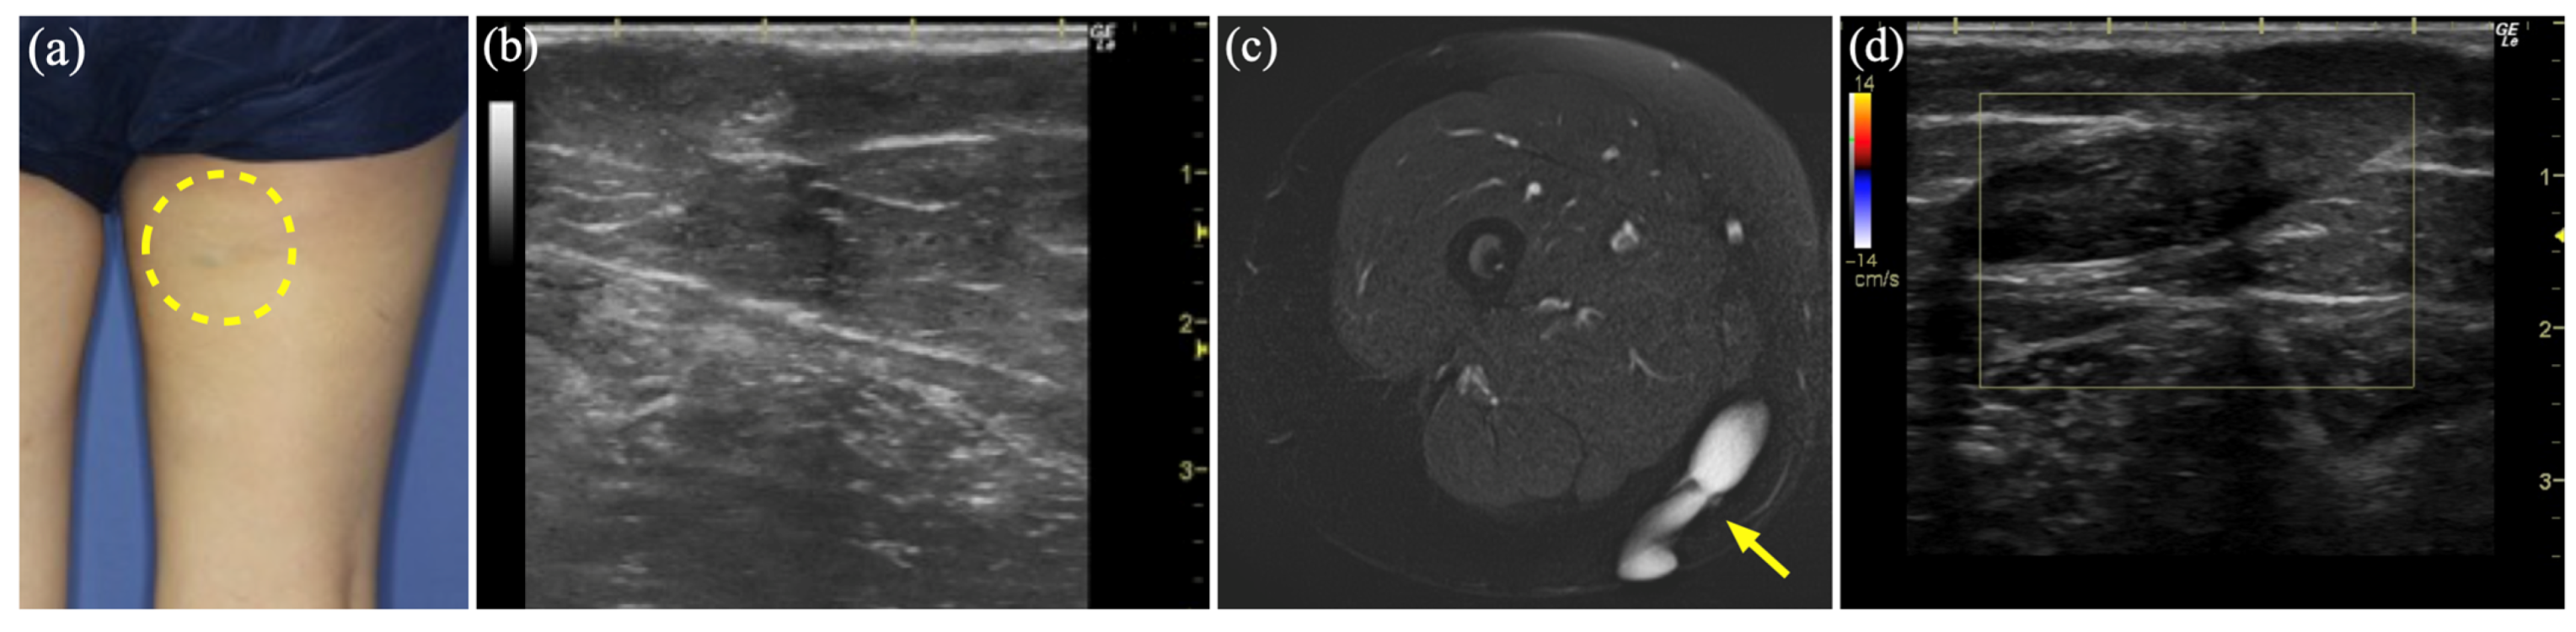

3.7. Case 9

| 9 | 66 | M | Rt hand | AVM | US, MR, 3D-CTA | None | Angiomyoma | 19 |